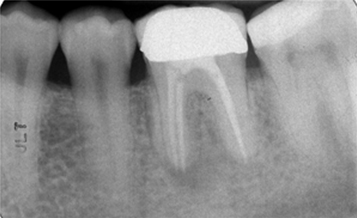

Following flapless extraction, a 3.6mm x 13.0mm implant was placed with an insertion torque value of 20 Ncm.

ISQ was recorded with a score of 66 with the Osstell device.

Initial ISQ of 66 at time of immediate placement